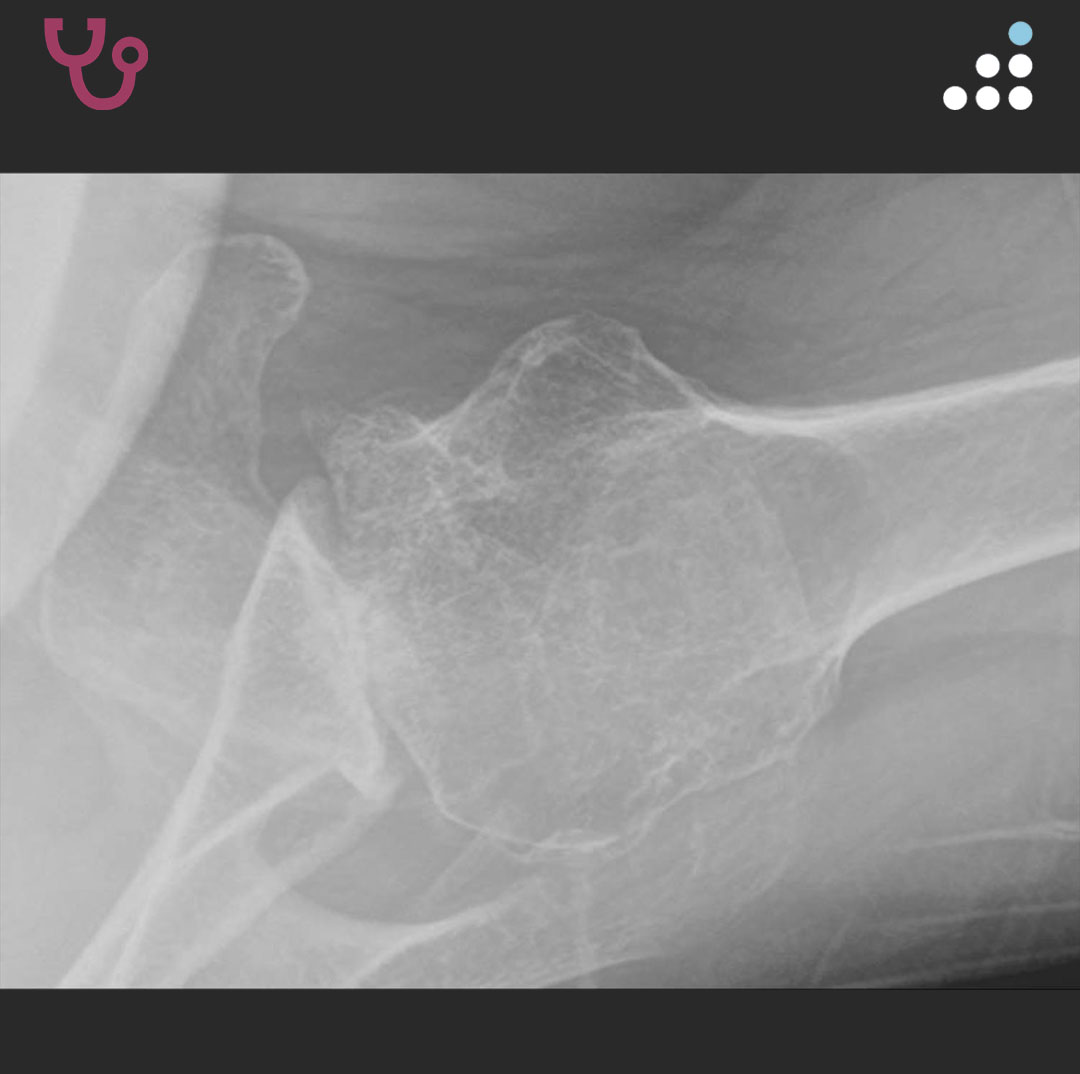

@orthobullets If there is still some cartilage left on the reverse Hill Sachs I’ve had some luck with doing a humeral head osteoplasty. I’ll use allograft chips or cement to backfill the defect after I tamp up articular surface and then try to get everything repaired especially in young pts